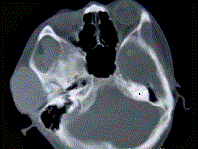

问题 19岁,女性患者,右侧面颊部肿胀一年,CT检查如图所示,请选择最佳答案 ( )

选项 A、右颊部横纹肌肉瘤 B、右颊部血肿 C、右颊部血管瘤 D、右颊部脂肪瘤 E、右颊部神经纤维瘤

答案 C